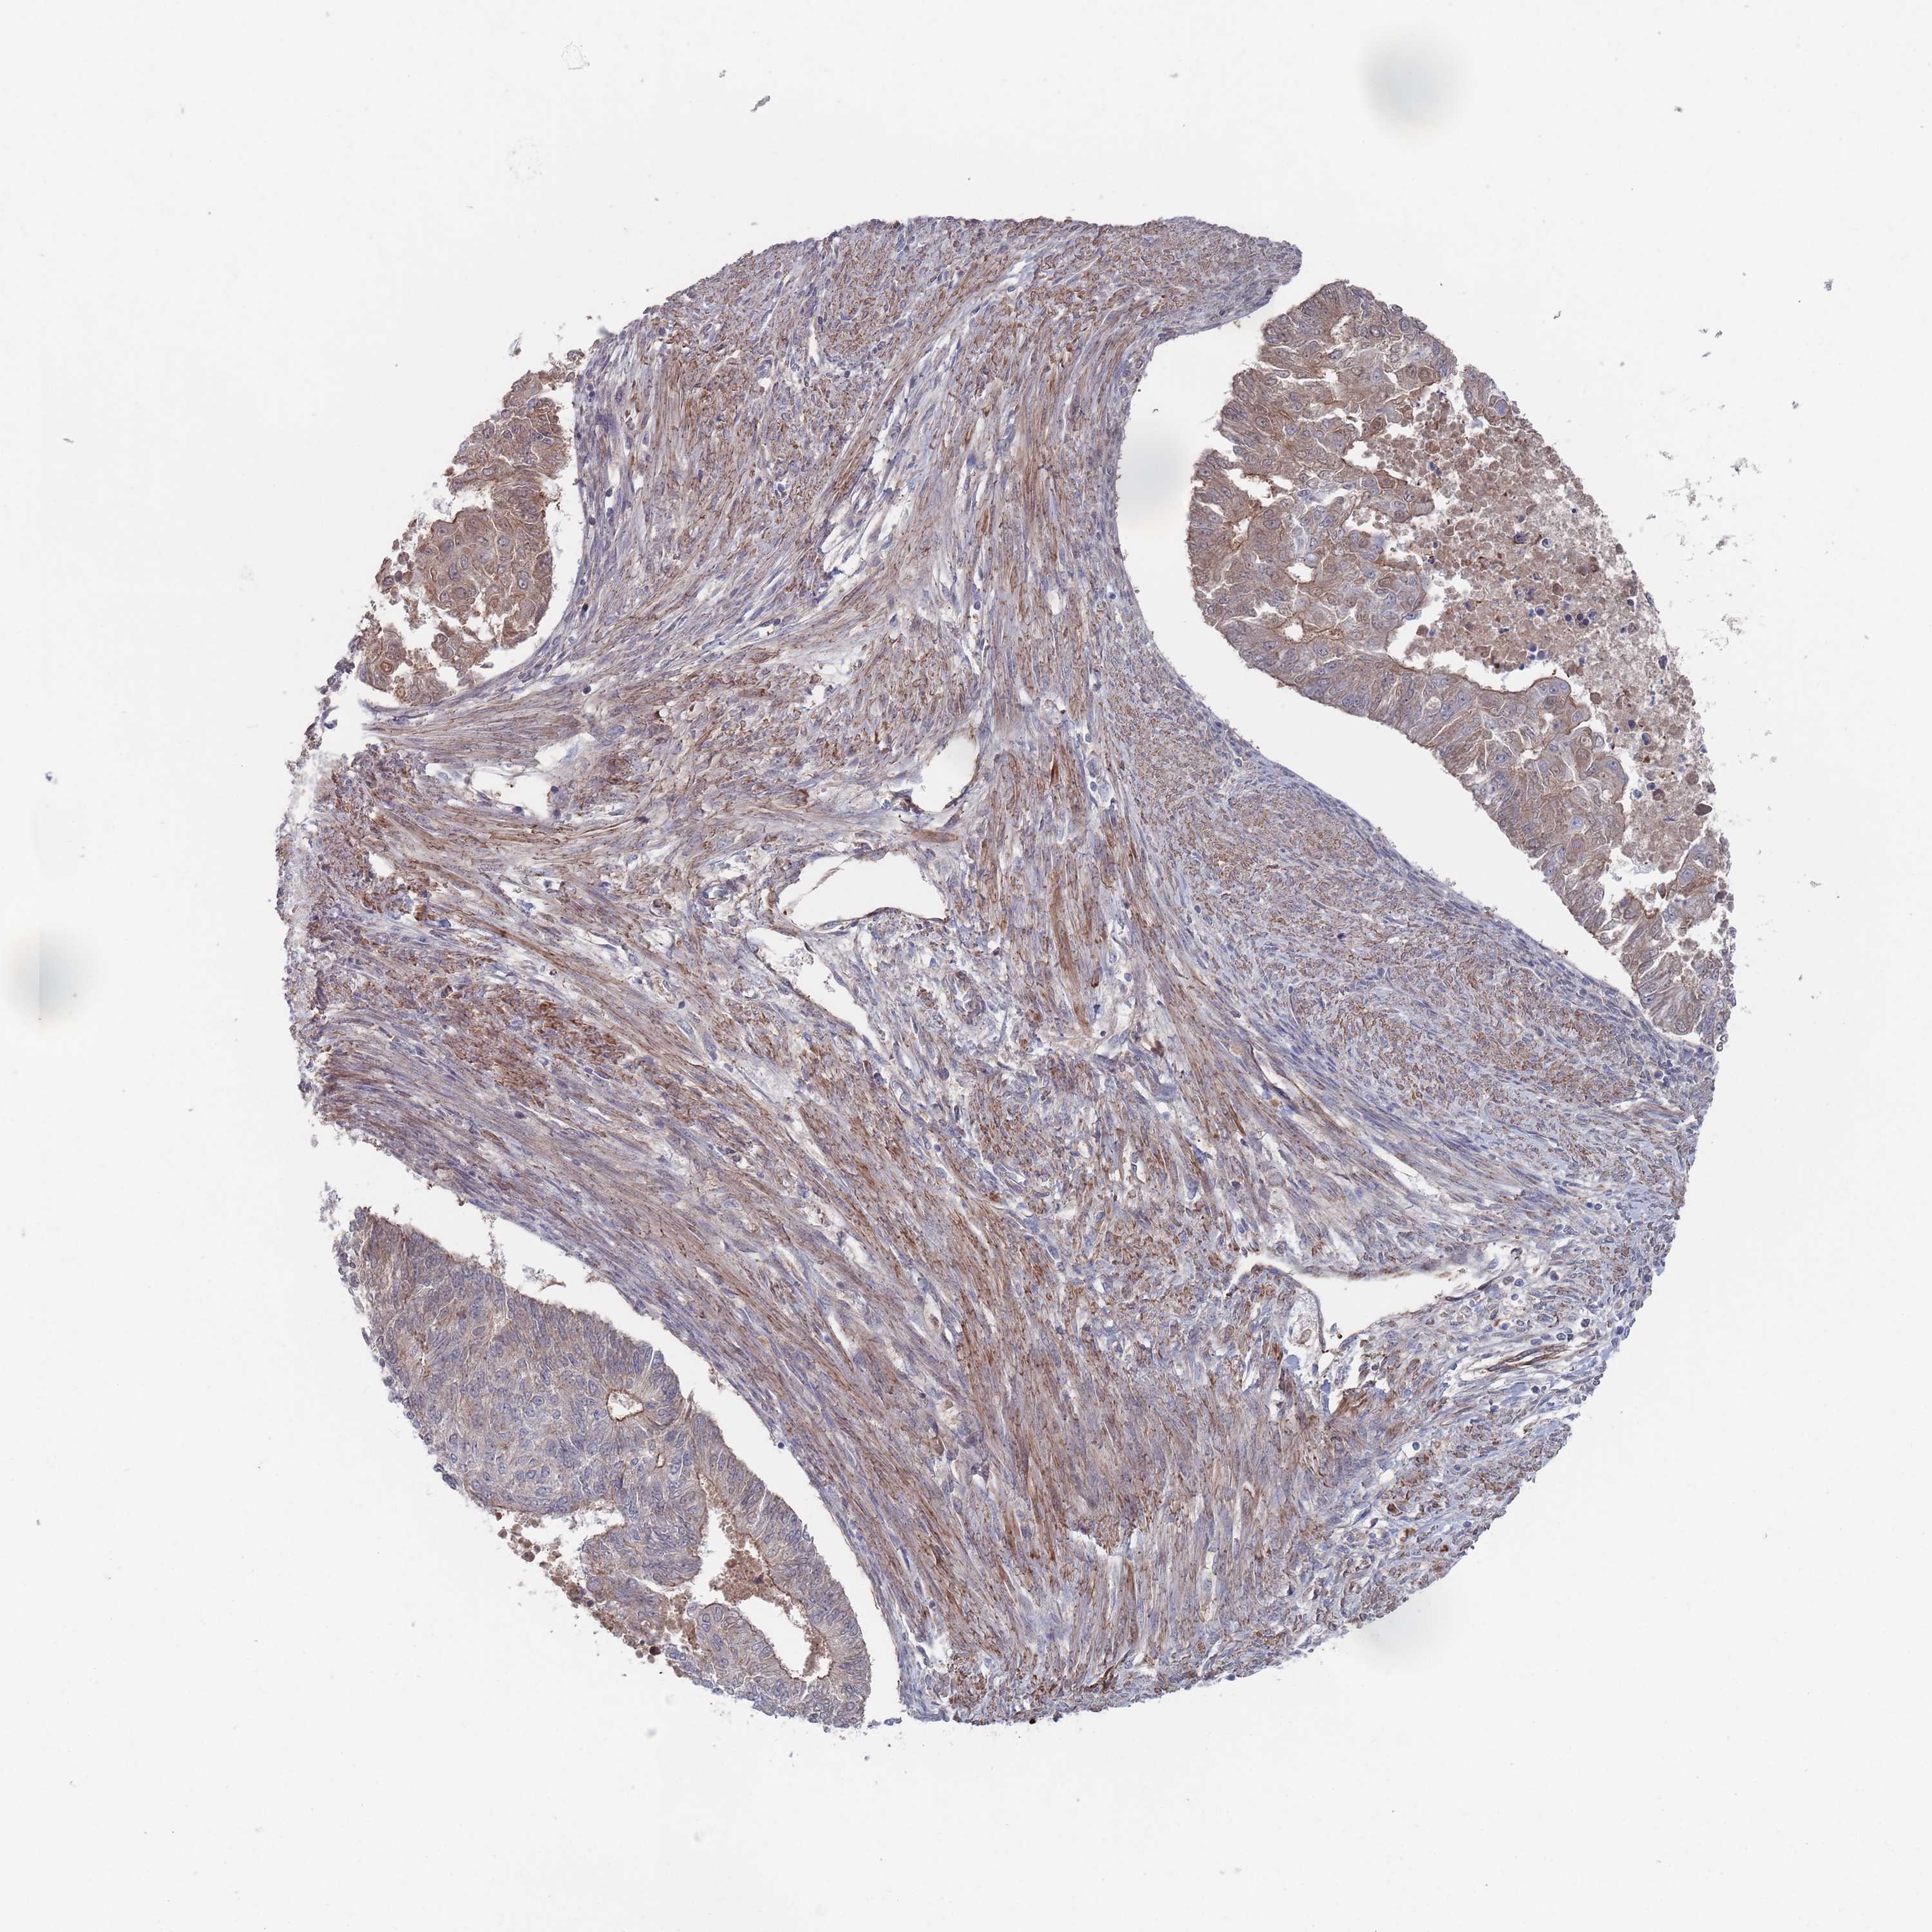

ENDOMETRIAL CANCER - Protein expressioni

A mouse-over function shows sample information and annotation data. Click on an image to view it in a full screen mode. Samples can be filtered based on level of antibody staining by selecting one or several of the following categories: high, medium, low and not detected. The assay and annotation is described here.

Note that samples used for immunohistochemistry by the Human Protein Atlas do not correspond to samples in the TCGA dataset.

Antibody stainingi

Antibody staining in the annotated cell types in the current human tissue is reported as not detected, low, medium, or high, based on conventional immunohistochemistry profiling in selected tissues. This score is based on the combination of the staining intensity and fraction of stained cells.

Each image is clickable and will lead to virtual microscopy that enables deeper exploration of all samples and also displays staining intensity scores, fraction scores and subcellular localization as well as patient and tissue information for each sample.

Antibody HPA042978

Antibody HPA048473

Staining

High

Medium

Low

Not detected

Intensity

Strong

Moderate

Weak

Negative

Quantity

>75%

75%-25%

<25%

None

Location

Nuclear

Cytoplasmic/membranous

Cytoplasmic/membranous,nuclear

Adenocarcinoma, NOS